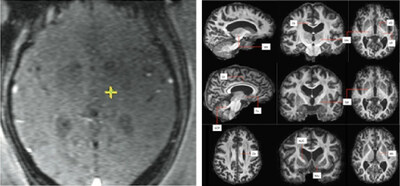

Now, a new technique using FAT1 imaging – a sophisticated MRI approach that fuses multiple scan types – is offering hope to patients.

A study in BMJ Neurology Open study reports the first use of FAT1 imaging to guide focused ultrasound for essential tremor. Traditionally, clinicians have relied on generalised brain maps to estimate the location of the target area within the brain – the Ventral Intermediate Nucleus (Vim) – which is extremely small and hard to visualise on standard MRI scans.

FAT1 imaging overcomes this by giving surgeons a direct view of the individual patient’s Vim, enabling treatment to be precise.

“FAT1 imaging is a game-changer,” said Mr Harith Akram, a consultant neurosurgeon at Queen Square Imaging who developed the technique and led the research. “By improving the visibility of the brain structures we need to target, we can deliver this non-invasive treatment with greater accuracy, faster results and fewer side effects, making a meaningful difference to patients’ lives.”